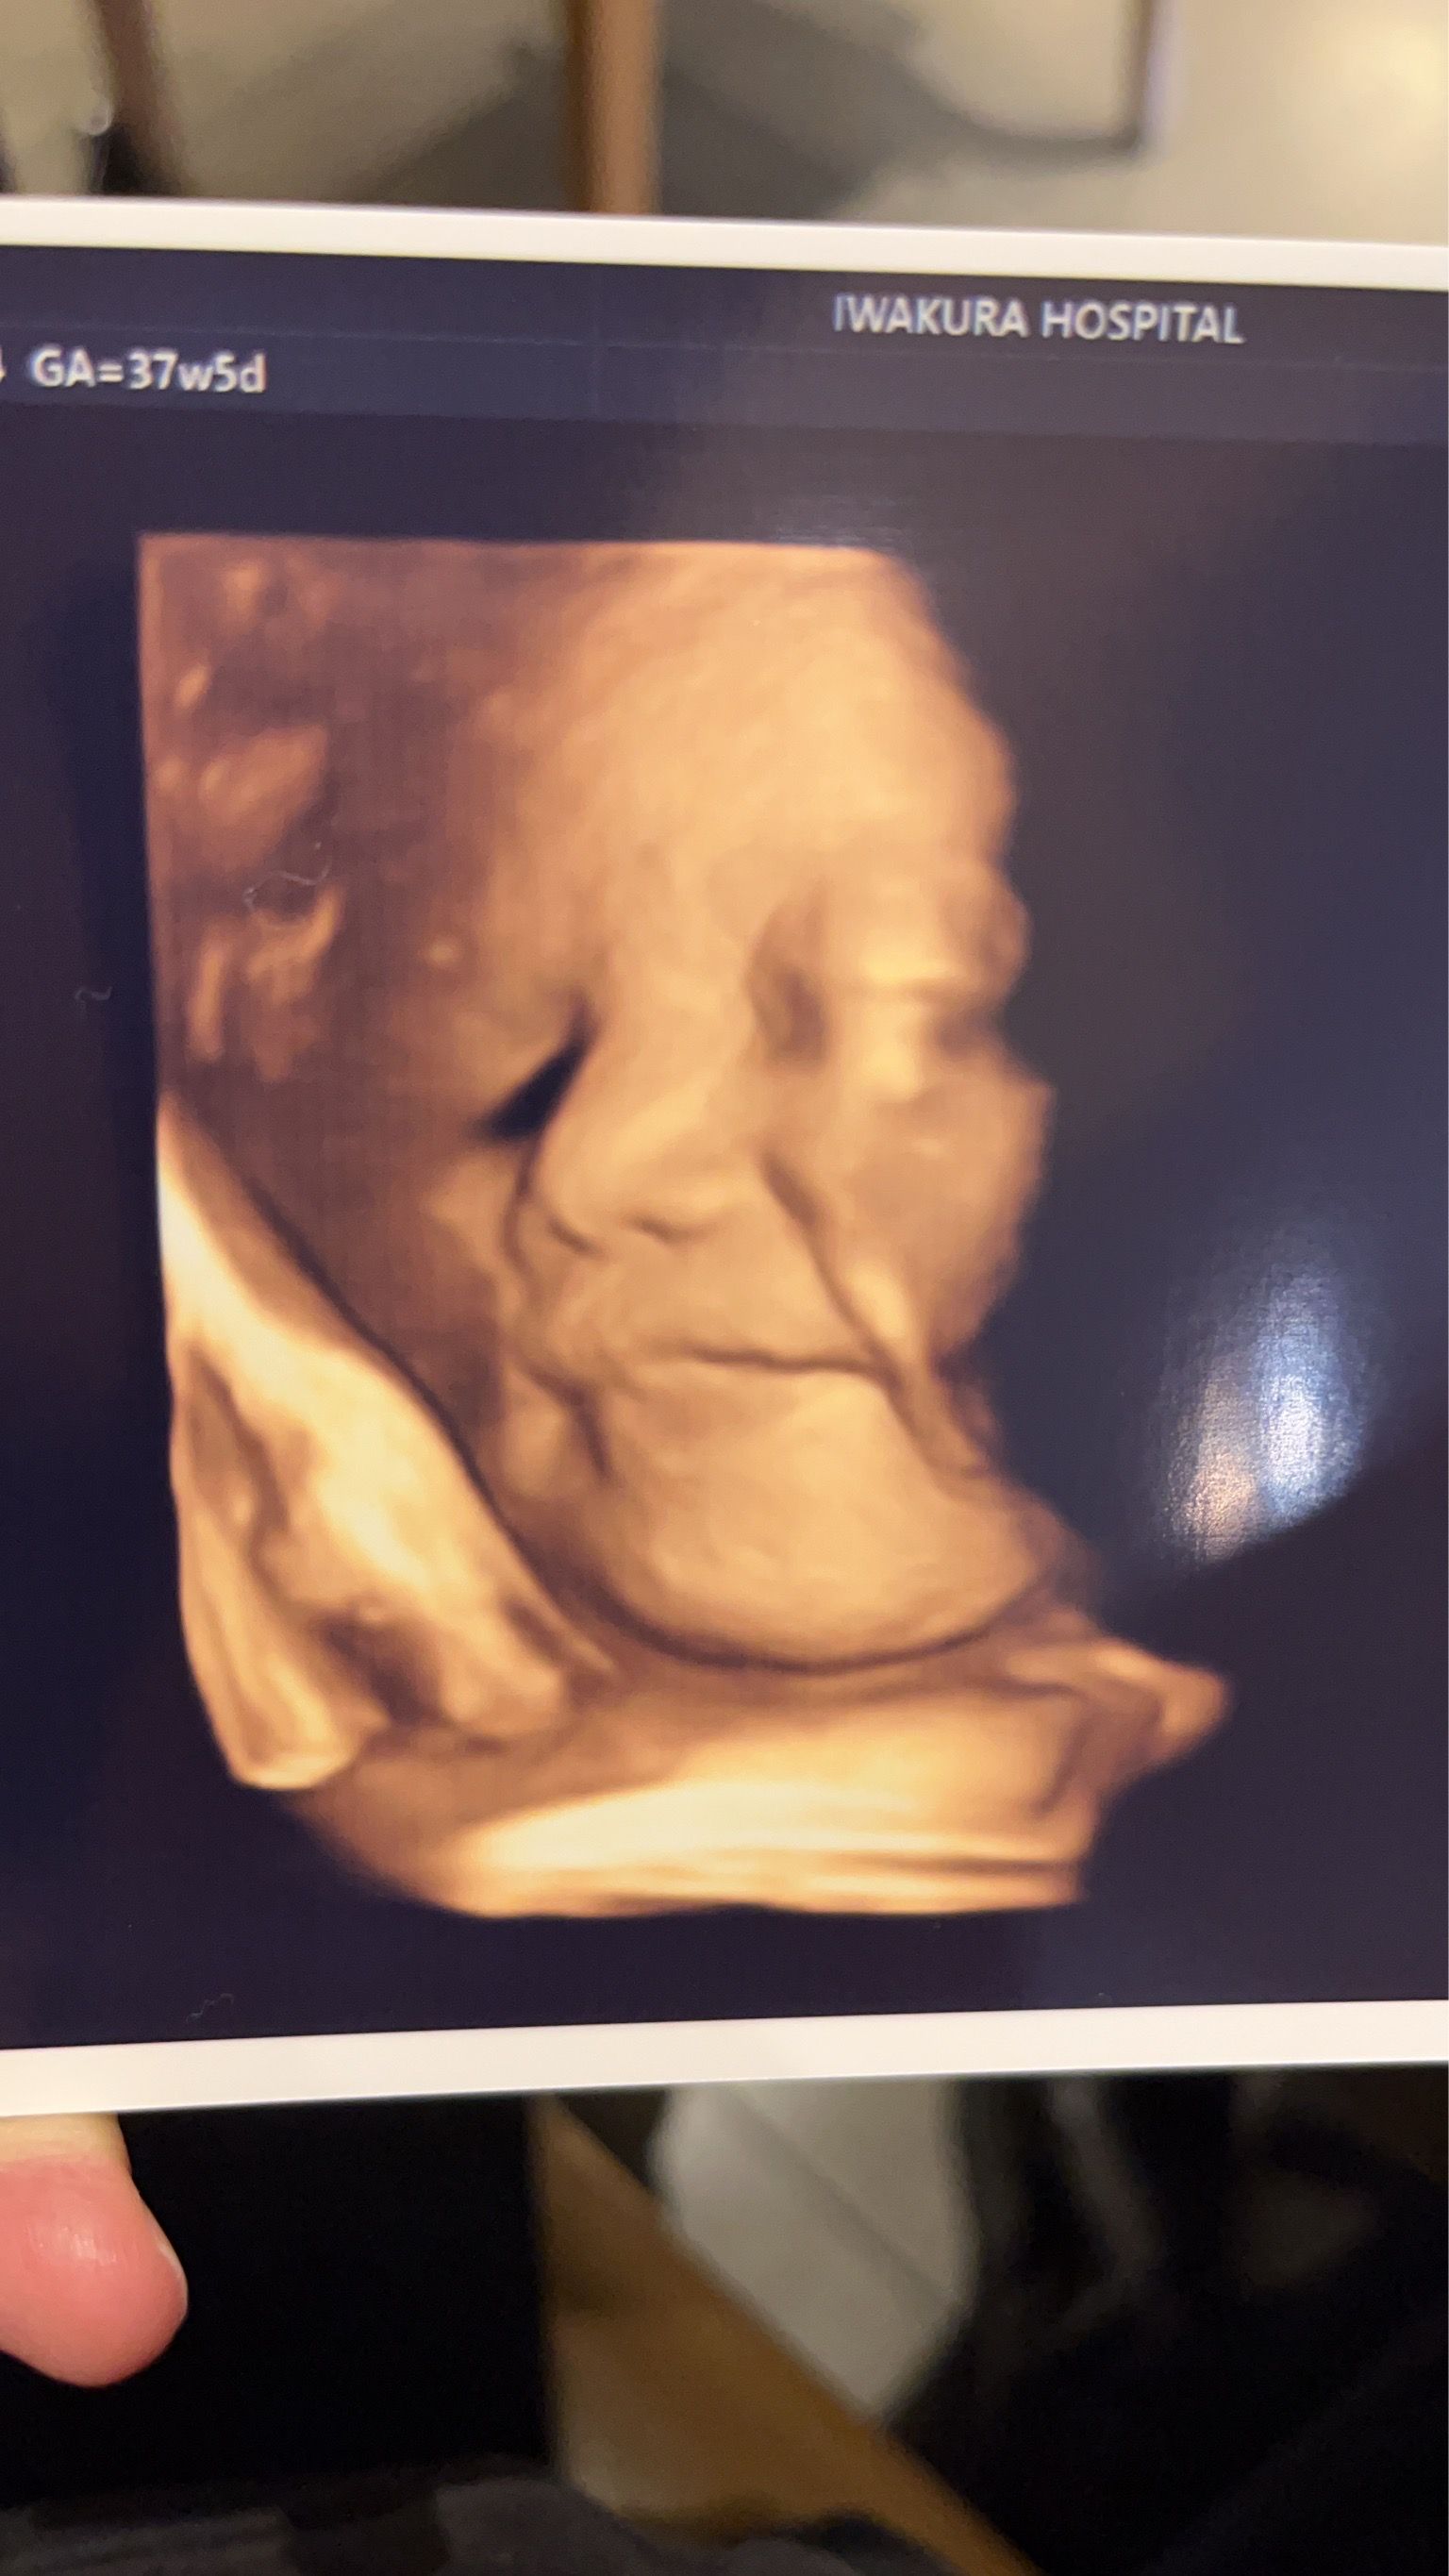

4Dエコー

"いつでもどこでもおなかの赤ちゃんに会える"

撮影したエコー動画をWebで閲覧できるサービス「echo diary(エコー ダイアリー)」を導入しています